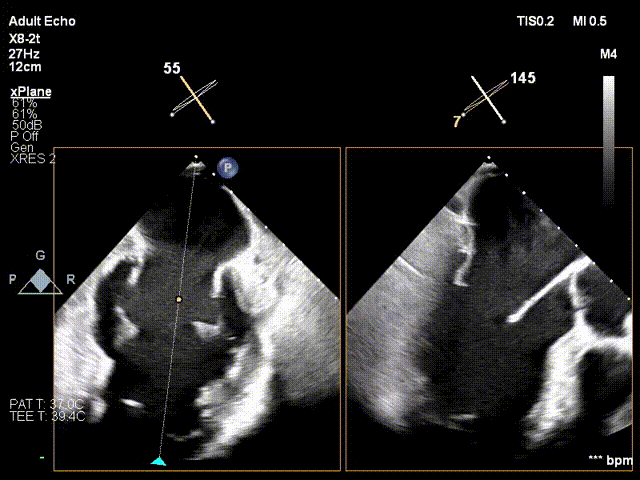

手术过程

于2偏3区置入第一枚短宽夹

调整Orientation至11点50方向

进入瓣下,捕捞瓣叶

瓣叶捕获,Buncing明显